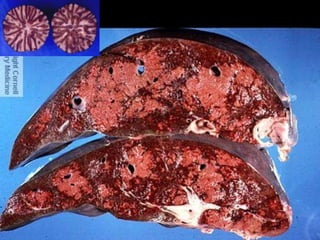

Alterações Circulatórias do Fígado  Congestão Hepática Passiva Crônica    I.C.C. Direita    Fígado em Noz-Moscada

Alterações Circulatórias doFígado  Congestão Hepática Passiva Crônica  I.C.C. Direita  Fígado em Noz-Moscada